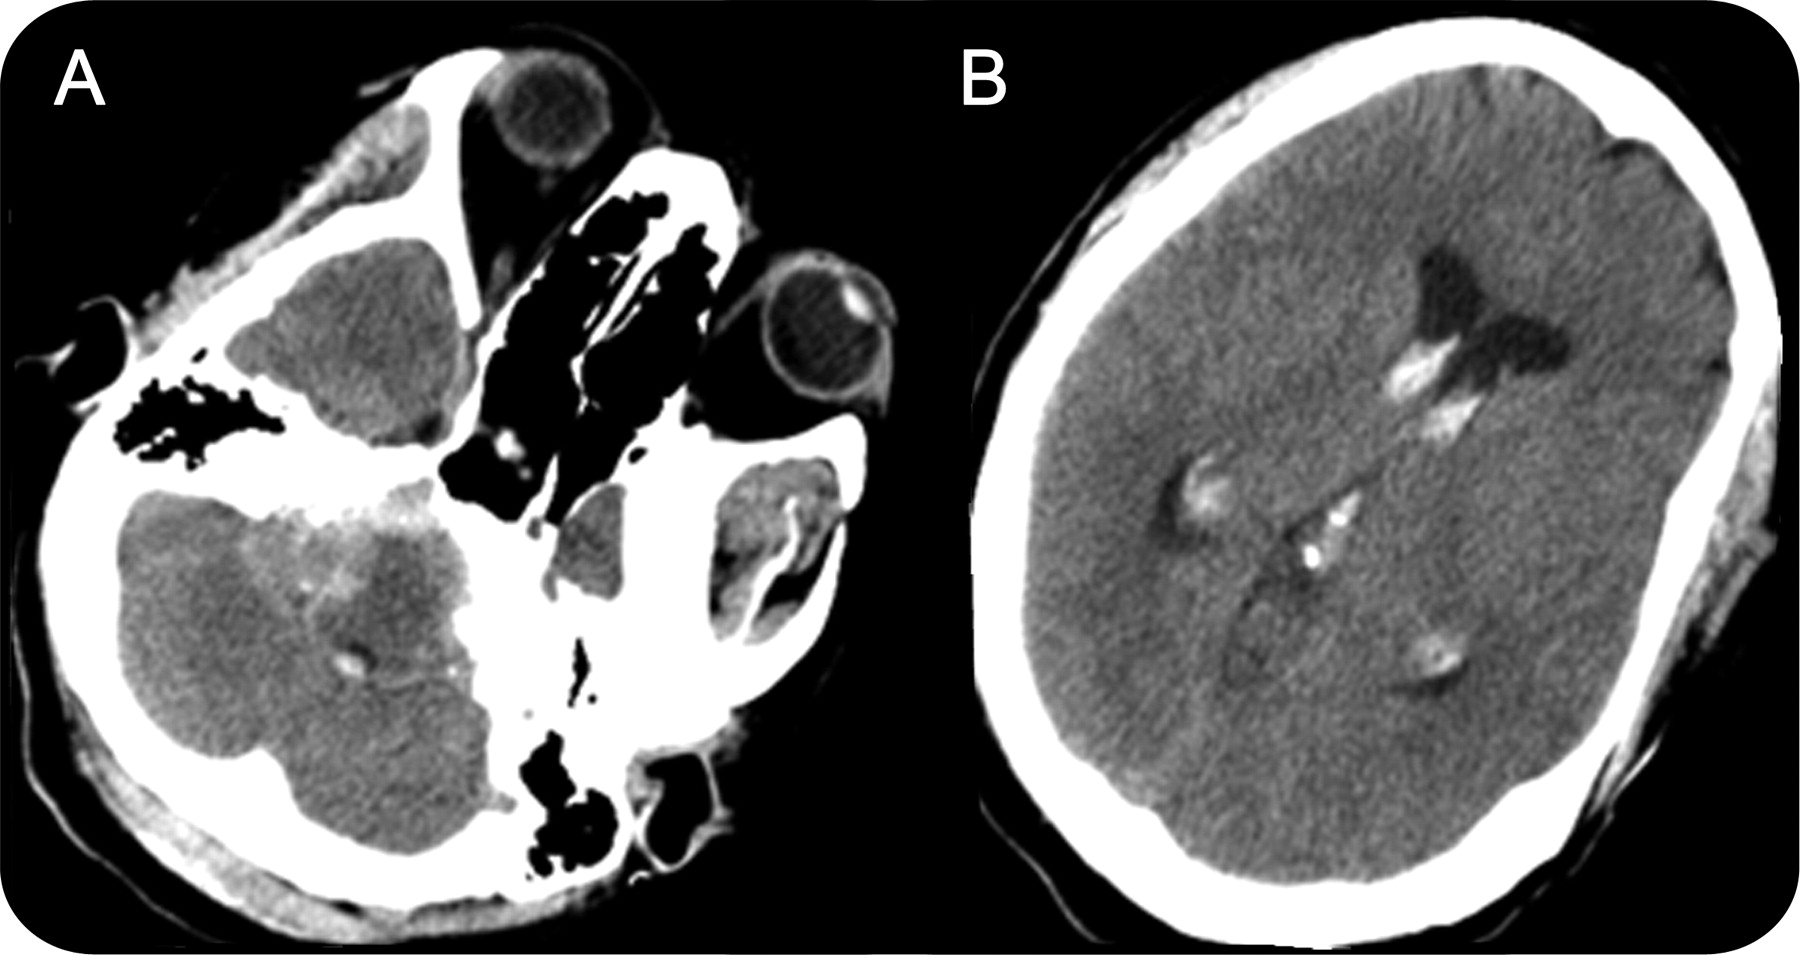

CT血管造影术的头部和颈部没有透露任何颅内动脉瘤或血管畸形(图2A和B)。然而,大量存在于正确的颞骨颈静脉孔与侵蚀和侵犯的权利内部声学运河。MRI证实其高血管性质量包含大量流动的空洞。质量位于外侧的髓质和扩展优小脑桥脑角水箱。它扩展下级向上级的方面对肿块空间和流离失所的右颈内动脉(图2C)。

(一)CT血管造影显示一个增强颈静脉孔质量扩展到颅后窝。(B)加强在颅底肿瘤的质量。(C)核磁共振t2加权图像显示满头花白的外观。(D)选择性右咽升血管造影横向视图显示一个hypervascularized肿瘤脸红,由两个主要从扩大右咽升动脉分支。

Catheter-based脑血管造影术显示一个强烈的其高血管性肿瘤脸红从上级方面正确的颈动脉鞘的头骨基地(图2D)。的主要喂养动脉分支内部上颌动脉,咽升动脉、耳后动脉。耳朵、鼻子和喉咙的评估显示红色的质量在中耳可见鼓膜和右声带麻痹性痴呆与最小的绑架。患者否认有任何声音沙哑,吞咽困难、构音障碍、或局灶性神经赤字。